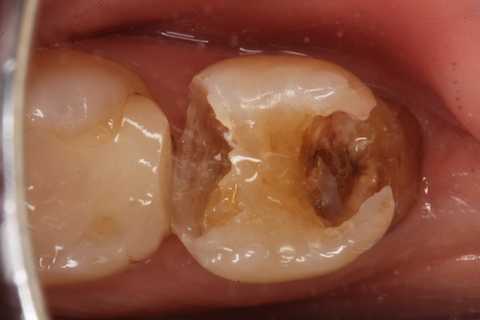

この症例は歯根内部をいじられていないので、根管治療は難しくない。CRで歯冠を再建するのが難しかった。

再建が終わった後で、内部の治療をしてCRで埋め戻している。